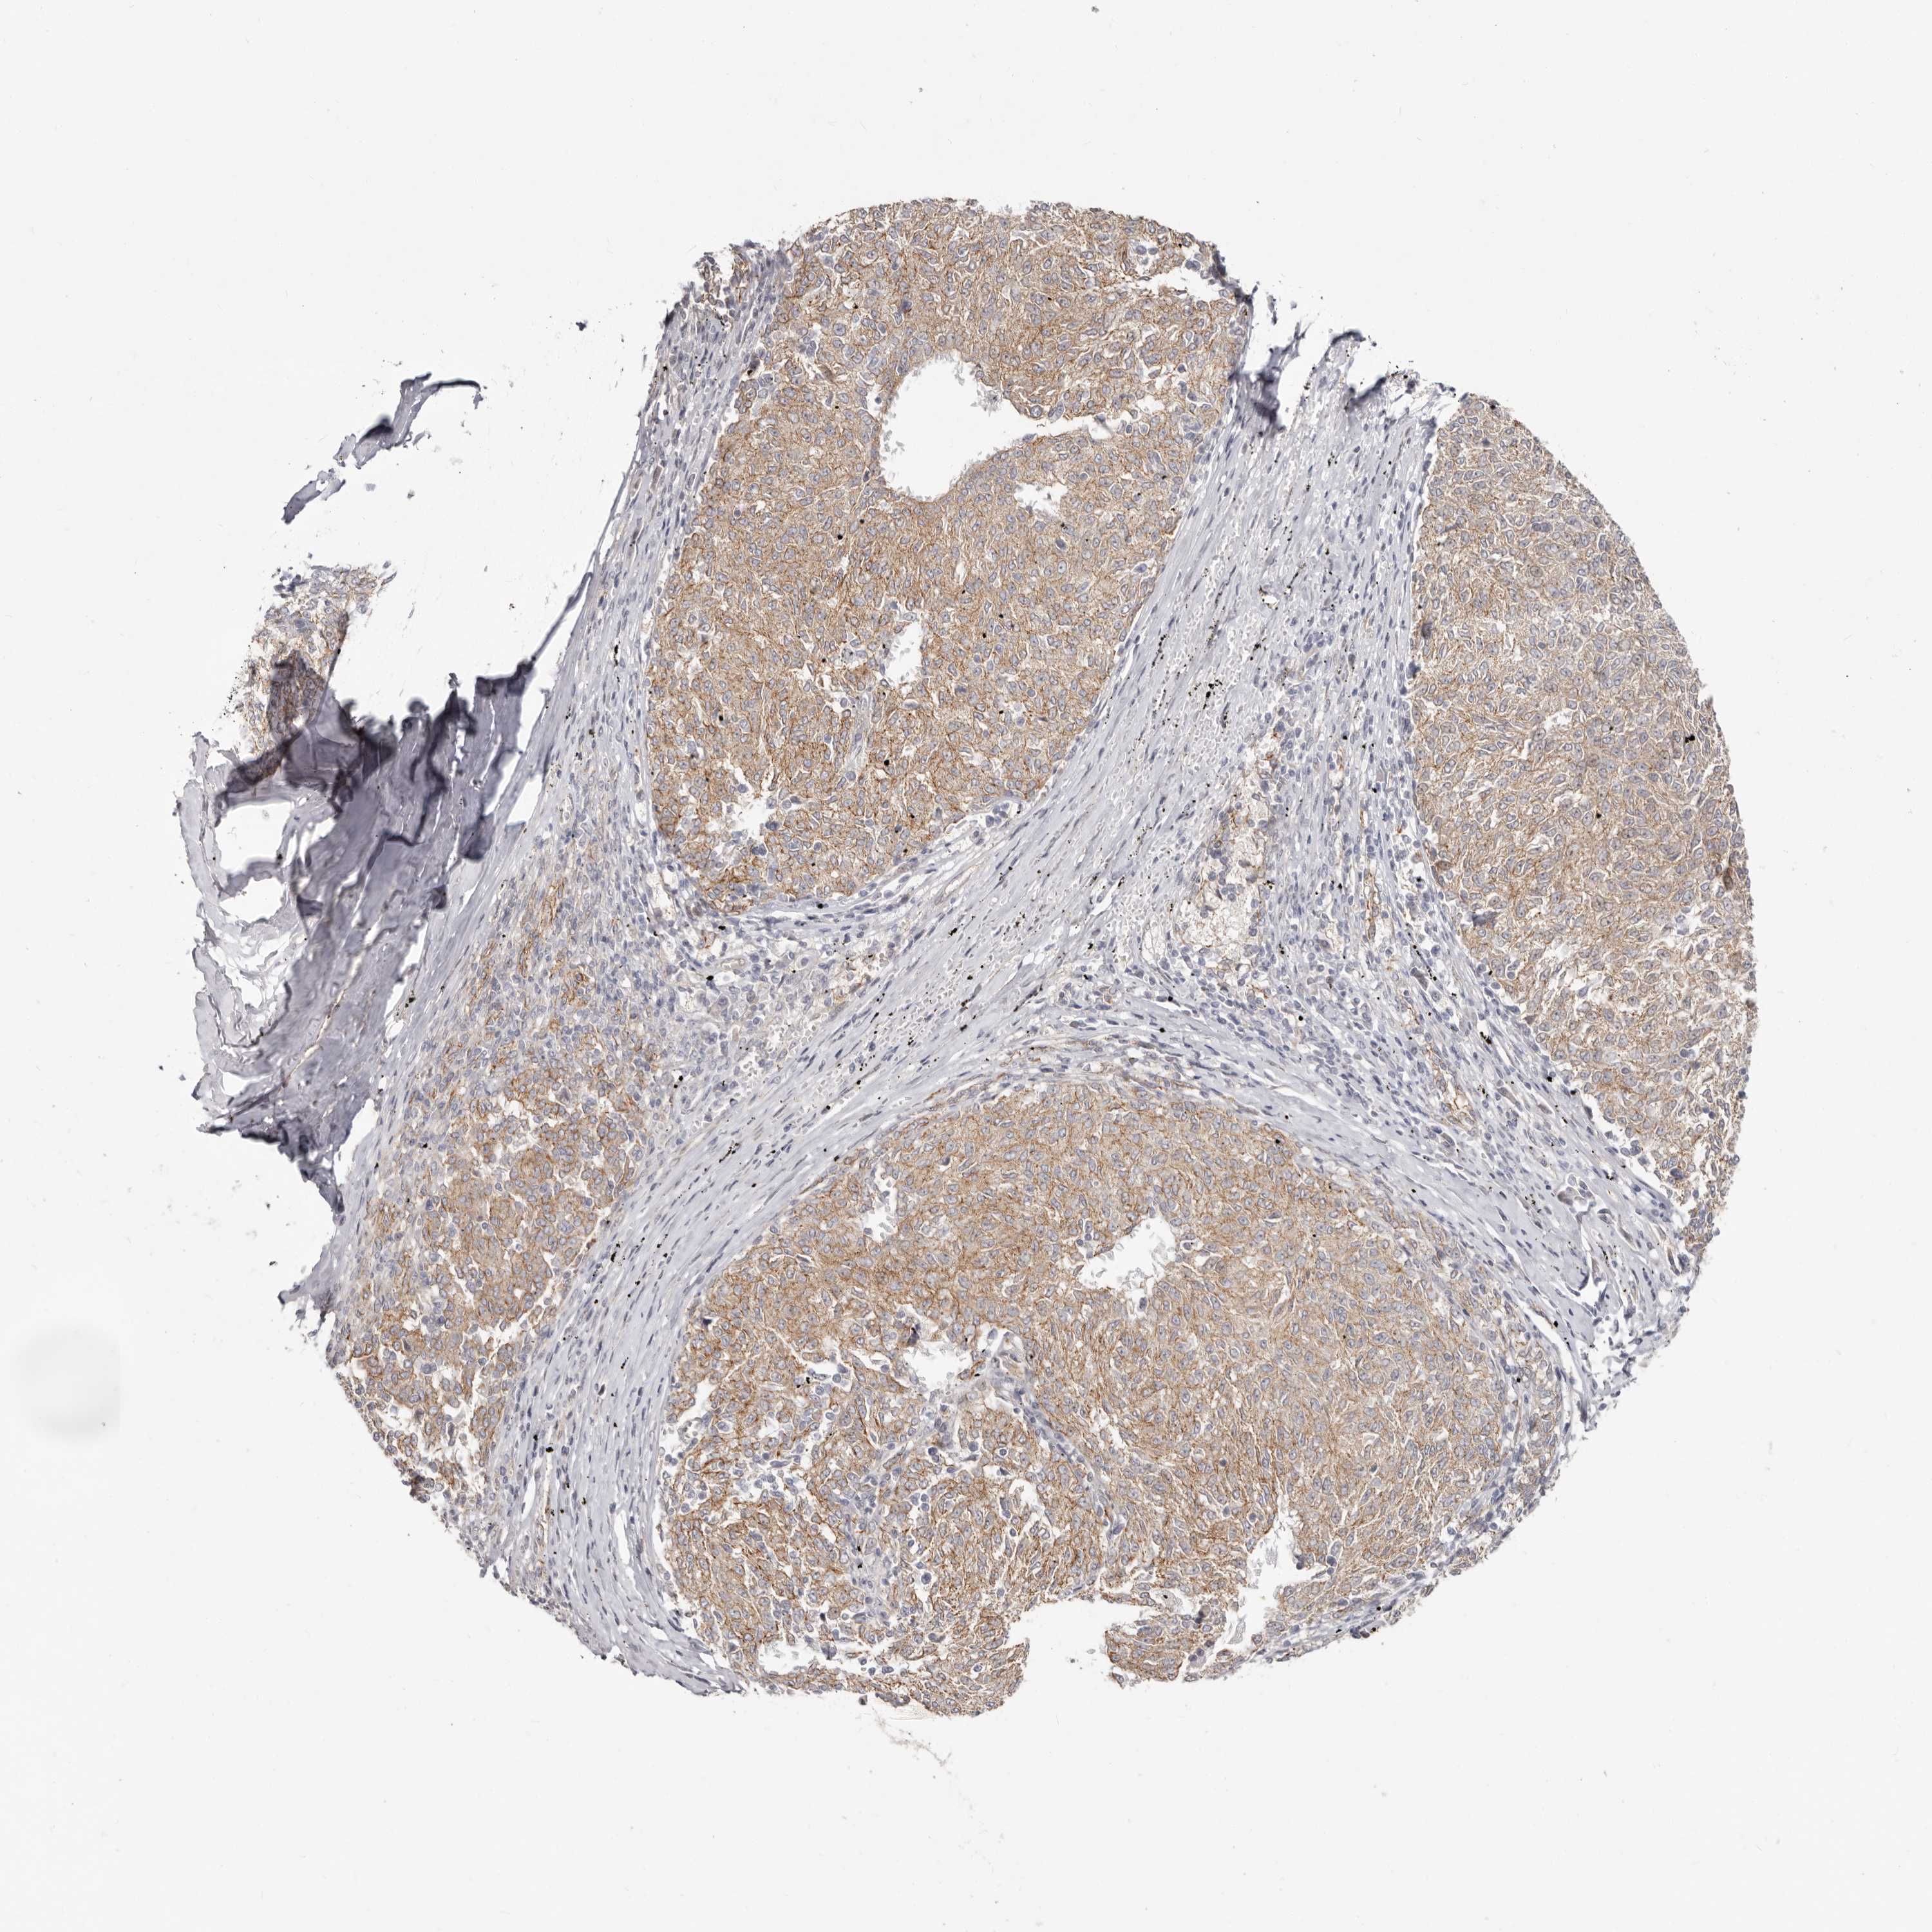

MELANOMA - Protein expressioni

A mouse-over function shows sample information and annotation data. Click on an image to view it in a full screen mode. Samples can be filtered based on level of antibody staining by selecting one or several of the following categories: high, medium, low and not detected. The assay and annotation is described here.

Note that samples used for immunohistochemistry by the Human Protein Atlas do not correspond to samples in the TCGA dataset.

Antibody stainingi

Antibody staining in the annotated cell types in the current human tissue is reported as not detected, low, medium, or high, based on conventional immunohistochemistry profiling in selected tissues. This score is based on the combination of the staining intensity and fraction of stained cells.

Each image is clickable and will lead to virtual microscopy that enables deeper exploration of all samples and also displays staining intensity scores, fraction scores and subcellular localization as well as patient and tissue information for each sample.

Antibody HPA029012

Staining

High

Medium

Low

Not detected

Intensity

Strong

Moderate

Weak

Negative

Quantity

>75%

75%-25%

<25%

None

Location

Nuclear

Cytoplasmic/membranous

Cytoplasmic/membranous,nuclear

Malignant melanoma, NOS

Malignant melanoma, Metastatic site